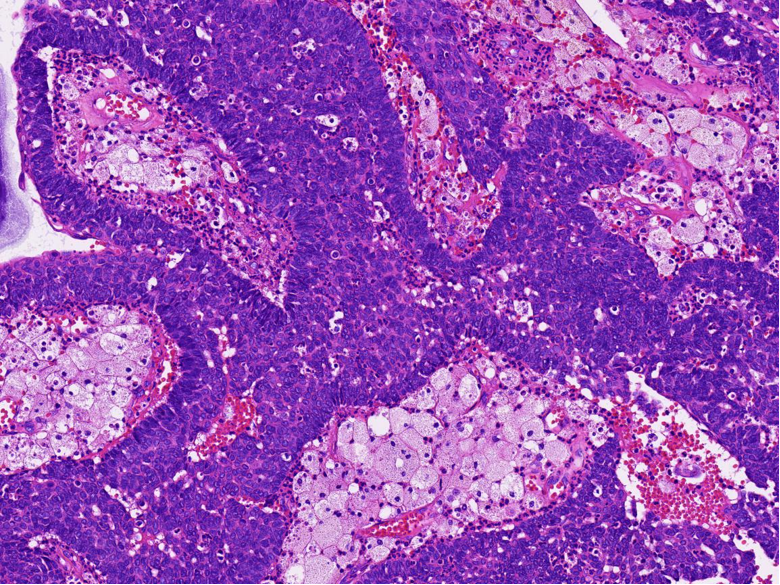

病理特征:宽薄乳头、 迷宫样内翻生长、单一肿瘤细胞形态、棘层松解、显著中性粒细胞浸润;

可见:细胞旋涡、透明细胞变、微囊形成、黏液纤毛上皮帽、部分肿瘤细胞异型性增加、坏死。

具有纤毛上皮帽